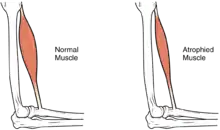

In the long term, the loss of muscle function can have additional effects from disuse, including atrophy of the muscle. Immobility can lead to pressure sores, particularly in bony areas, requiring precautions such as extra cushioning and turning in bed every two hours (in the acute setting) to relieve pressure.[51] In the long term, people in wheelchairs must shift periodically to relieve pressure.[52] Another complication is pain, including nociceptive pain (indication of potential or actual tissue damage) and neuropathic pain, when nerves affected by damage convey erroneous pain signals in the absence of noxious stimuli.[53] Spasticity, the uncontrollable tensing of muscles below the level of injury, occurs in 65–78% of chronic SCI.[54] It results from lack of input from the brain that quells muscle responses to stretch reflexes.[55] It can be treated with drugs and physical therapy.[55] Spasticity increases the risk of contractures (shortening of muscles, tendons, or ligaments that result from lack of use of a limb); this problem can be prevented by moving the limb through its full range of motion multiple times a day.[56] Another problem lack of mobility can cause is loss of bone density and changes in bone structure.[57][58] Loss of bone density (bone demineralization), thought to be due to lack of input from weakened or paralysed muscles, can increase the risk of fractures.[59] Conversely, a poorly understood phenomenon is the overgrowth of bone tissue in soft tissue areas, called heterotopic ossification.[60] It occurs below the level of injury, possibly as a result of inflammation, and happens to a clinically significant extent in 27% of people.[60]